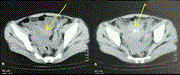

Intramuscular abdominal hibernoma: case report of a rare tumour and a review of the literature

Hooman Baghaie and others

Journal of Surgical Case Reports, Volume 2021, Issue 2, February 2021, rjaa304, https://doi.org/10.1093/jscr/rjaa304